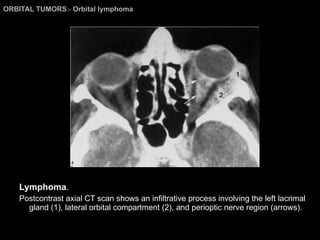

ORBITAL TUMORS >  Orbital lymphoma Lymphoma . Postcontrast axial CT scan shows an infiltrative process involving the left lacrimal gland (1), lateral orbital compartment (2), and perioptic nerve region (arrows).